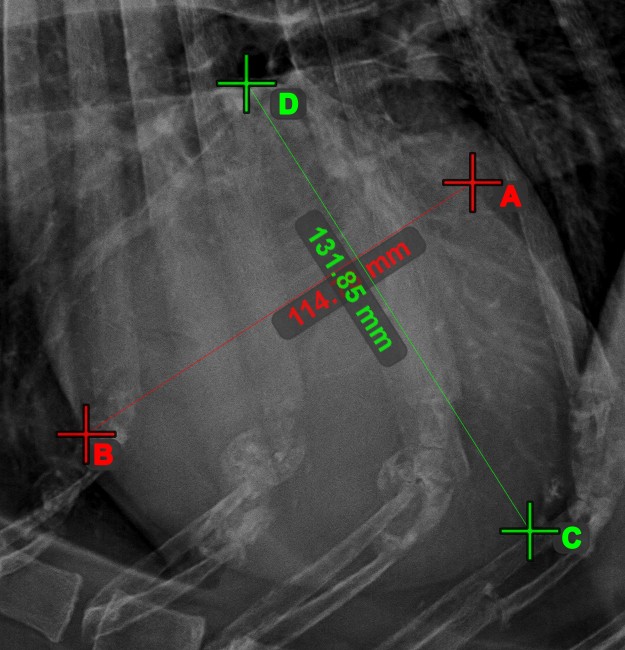

Quickly and accurately locate and mark the intersection point between two existing lines by using the Line Intersection tool.

Select the tool from the left toolbar and assign it to one of the available mouse buttons. Select two lines that have already been drawn on the scene to complete the measurement. The intersection point of the line will be automatically calculated and marked on the scene. The intersection point of two lines will always be marked with the letter X.

If two lines do not intersect directly, the intersection point of their extended projections on the scene will be marked.